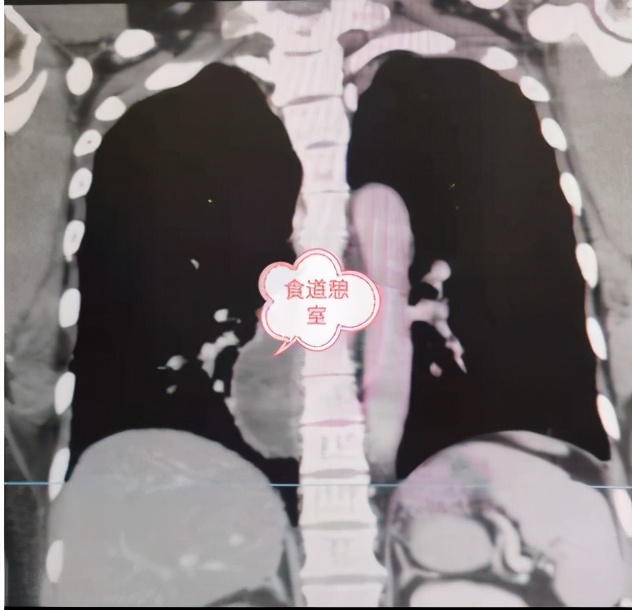

患者耿某,女,46岁,盘州市松河乡人,1个月前无明显诱因出现进食后胸部疼痛,为阵发性烧灼样疼痛,到该院心胸泌尿外科住院治疗。据悉,耿某一年前接受过纵膈肿瘤切除手术。住院期间完善胸腹部CT、胃镜、食道造影检查,明确诊断为“食道下段憩室”。

本次手术由该院副院长付强主刀,该科团队配合实施完成。手术过程分两步:首先,取左胸后外侧切口沿第七肋上缘进胸,探查见食管下段憩室大小为7cmX4cm,充分分离后切除;而后行食管与胃部进行吻合重建术,术中出血较少,患者各生命体征均正常,手术历时5个小时,非常成功。术后,在医护人员的精心护理和治疗下,耿某恢复良好。